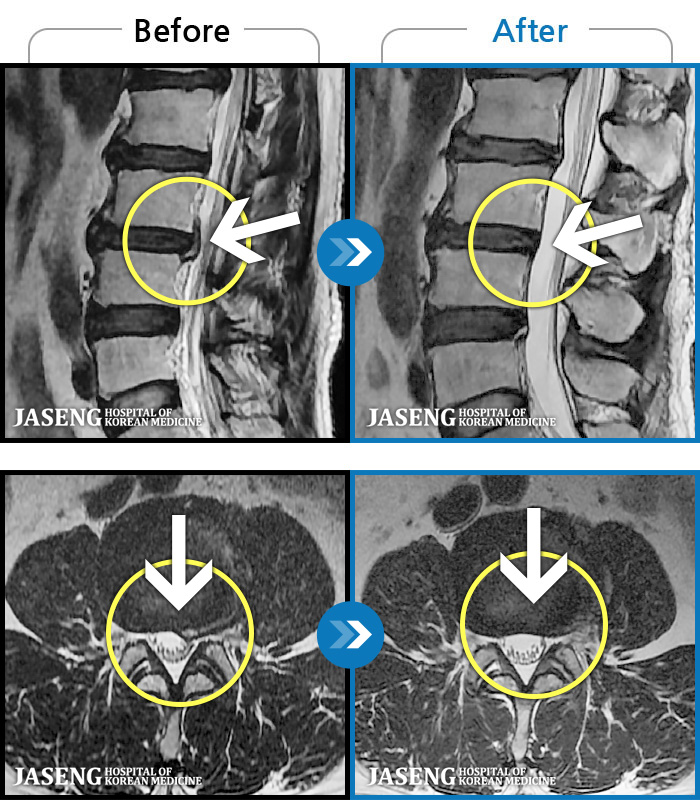

ȯںп Ǹ ǿ ԿǾ, ο ġ ۿ Ƿ ġḦ Ͻñ ٶϴ.